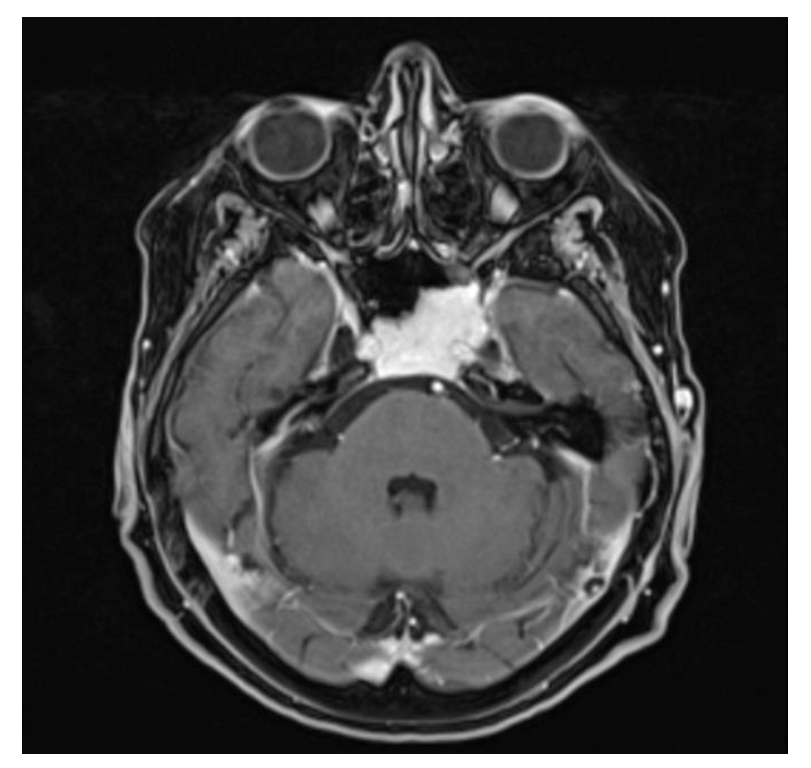

3.2. Case 2—Ecchordosis Physaliphora

3.3. Case 3—Hepatocellular Carcinoma Metastasis